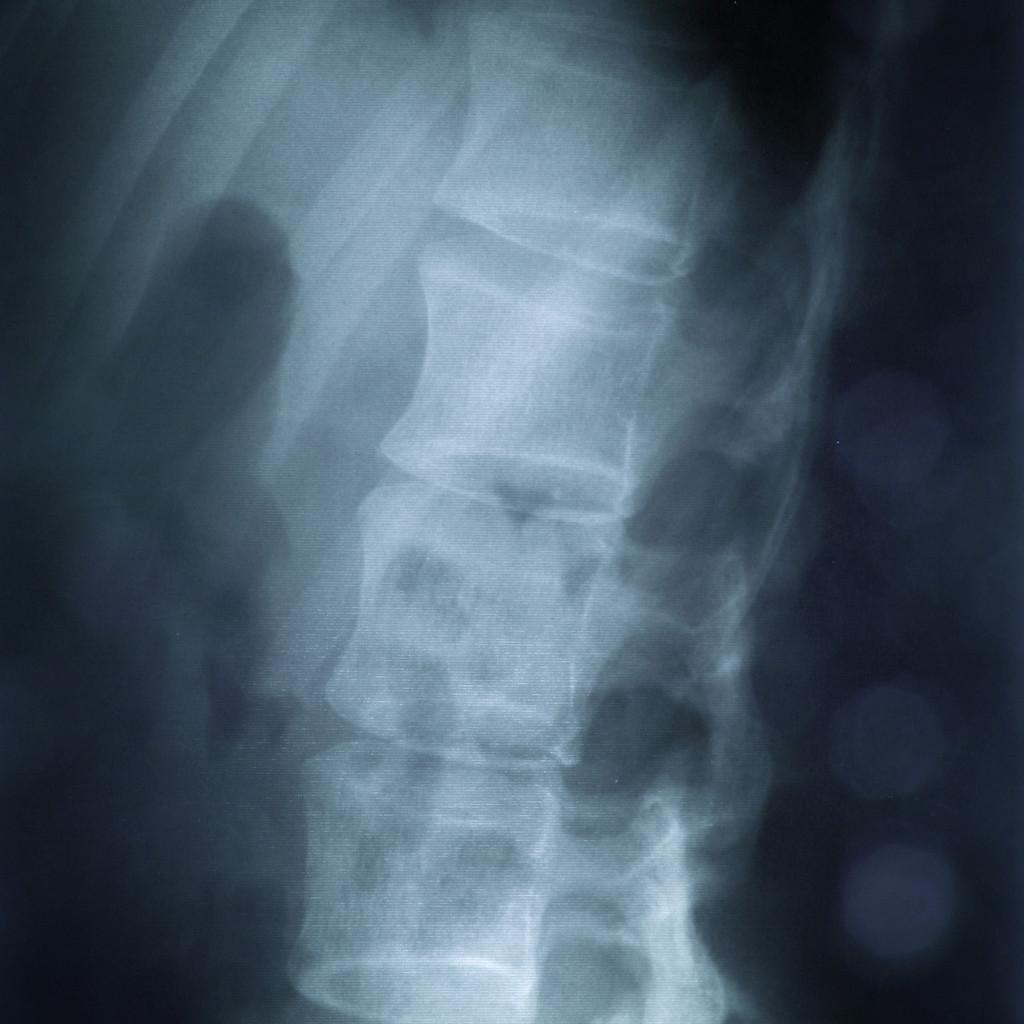

1、脊椎X线平片

显示脊柱裂的骨性结构改变。椎间孔在隆起囊伸展至胸腔、腹腔时常增大,而在骶管突出至盆腔时则明显增大。